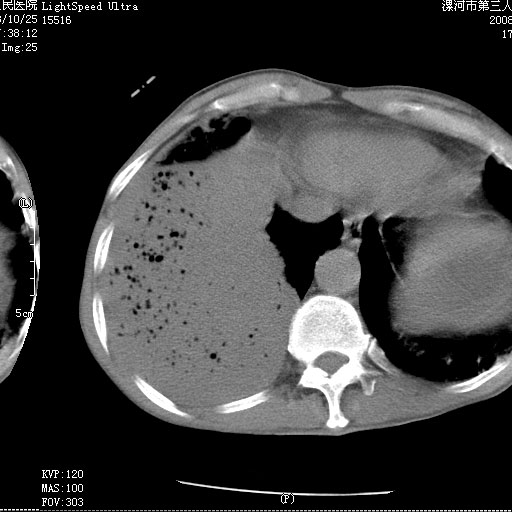

m 老年 发烧、呼吸困难,慢支、肺气肿多年;记的那次是下午大概17:38做的,晚上窒息死亡。

上面的层面就慢性支气管炎肺气肿、肺大泡,别的没有什么、也就不传了。

当时我怀疑:1、阻塞性肺不张早期 2、肺脓肿早期,望老师们发表意见

1、右侧脓胸;2、copd;

3、细支气管肺泡癌可以排除,病变以斜裂为界,呈大片状高密度影,内可见多发小气泡,表明有产气杆菌感染所致,内无明显的支气管“枯树枝征”表现,再结合其临床改变(细支气管肺泡癌临表表现重、影像表现轻)所以不符合细支气管肺泡癌(炎症型)的改变。

病变按肺叶分布,病变内可见多个小空腔影,未见充气支气管影,中间段支气管管腔肺窗示密度欠均匀,下肺支气管分叉处基底段支气管隐约可见,未见明显狭窄,中叶支气管通畅,

考虑:阻塞性肺炎伴小脓肿形成可能性大。(痰栓可能性大)

右下肺实变,内有弥漫分面小气泡而无支气管征,叶间裂前移,呈臌大之形,而无收缩之状,兼纵隔稍左行移,故。不支持不张,倒支持大叶肺叶,如楼上所说,小气泡不象残留之肺,不可以考虑产气菌感染吗。

阻塞性肺炎,肺脓肿形成。依据,右下支气管不通,大片实变形内可见小气泡。不支持肺不张。

右下肺阻塞性炎症,内见多发气体影,以肺叶分布.不支持不张.